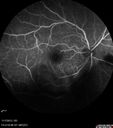

Patient states that he went to sleep on Thursday night 10/31 and when he woke up Friday morning he had a headache and some eye irritation in the right eye, along with decreased vision. This was about 1 week ago. It's doing about the same or a little bit worse. He started the eye drops about 2 days ago and one yesterday. He is on homatropine, timolol and durazol. Patient is now getting gamma-globulin. For the entire month of September he had 103 degree fever. He had a second opinion from a doctor at Moffit. There was suspicious that the T-Cell count was low. He was on prednisone and has now tapered to 5 mg per day. He is to taper off by Sunday. He started on high dose prednisone 60 mg per day in September. He has not had a port in for a few years. He had no indwelling catheters in the hospital. VA OD: sc20/125-2 PH20/40-2 NccJ10 OS: sc20/16 PHNI NccJ1+ IOP: TP OD: 21 OS: 14 Posterior Segment: Findings OD: Nerve: Pink. Sharp. CDR-V 0.5. Vitreous: Vitreous Syneresis. Mild Diffuse Cells. Retinal Vessels: Attenuated Vessels. Macula: No Hemorrhage. No Subretinal Fluid. No Edema. Because of the possible diagnoses, PCR was sent of the anterior chamber which came back positive for toxoplasmosis and negative for herpes viruses. The patient was treated with Bactrim DS for 6 weeks and no steroids and completely resolved. The lesion grew a little bit.

Toxoplasmosis Retinitis - Vitritis and Anerior Uveitis461 viewsFA shows Dark Spot00000

toxo_helo_11071319.jpg

Toxoplasmosis Retinitis - Vitritis and Anerior Uveitis420 viewsSerous Retinal Detachment Associated with Lesion00000

Toxoplasmosis Retinitis - Vitritis and Anerior Uveitis456 viewsSerous Retinal Detachment Associated with Lesion00000

Toxoplasmosis Retinitis - Vitritis and Anerior Uveitis436 viewsSerous Retinal Detachment Associated with Lesion00000